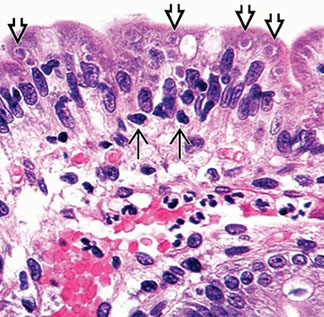

Giardia duodenalis

Giradia lamblia

aka G duodenalis or G intestinalis; described by Leeuwenhoek looking at his own poop; flagellated only need 10 cysts to infect; resistant to chlorine, thus endemic in unfiltered water

- pear-shaped, c 2 equal size nuclei, do not invade and sm bowel morphology may be normal, though can have inflam c heavy infx

Giardia trophozoites on mucosal surface